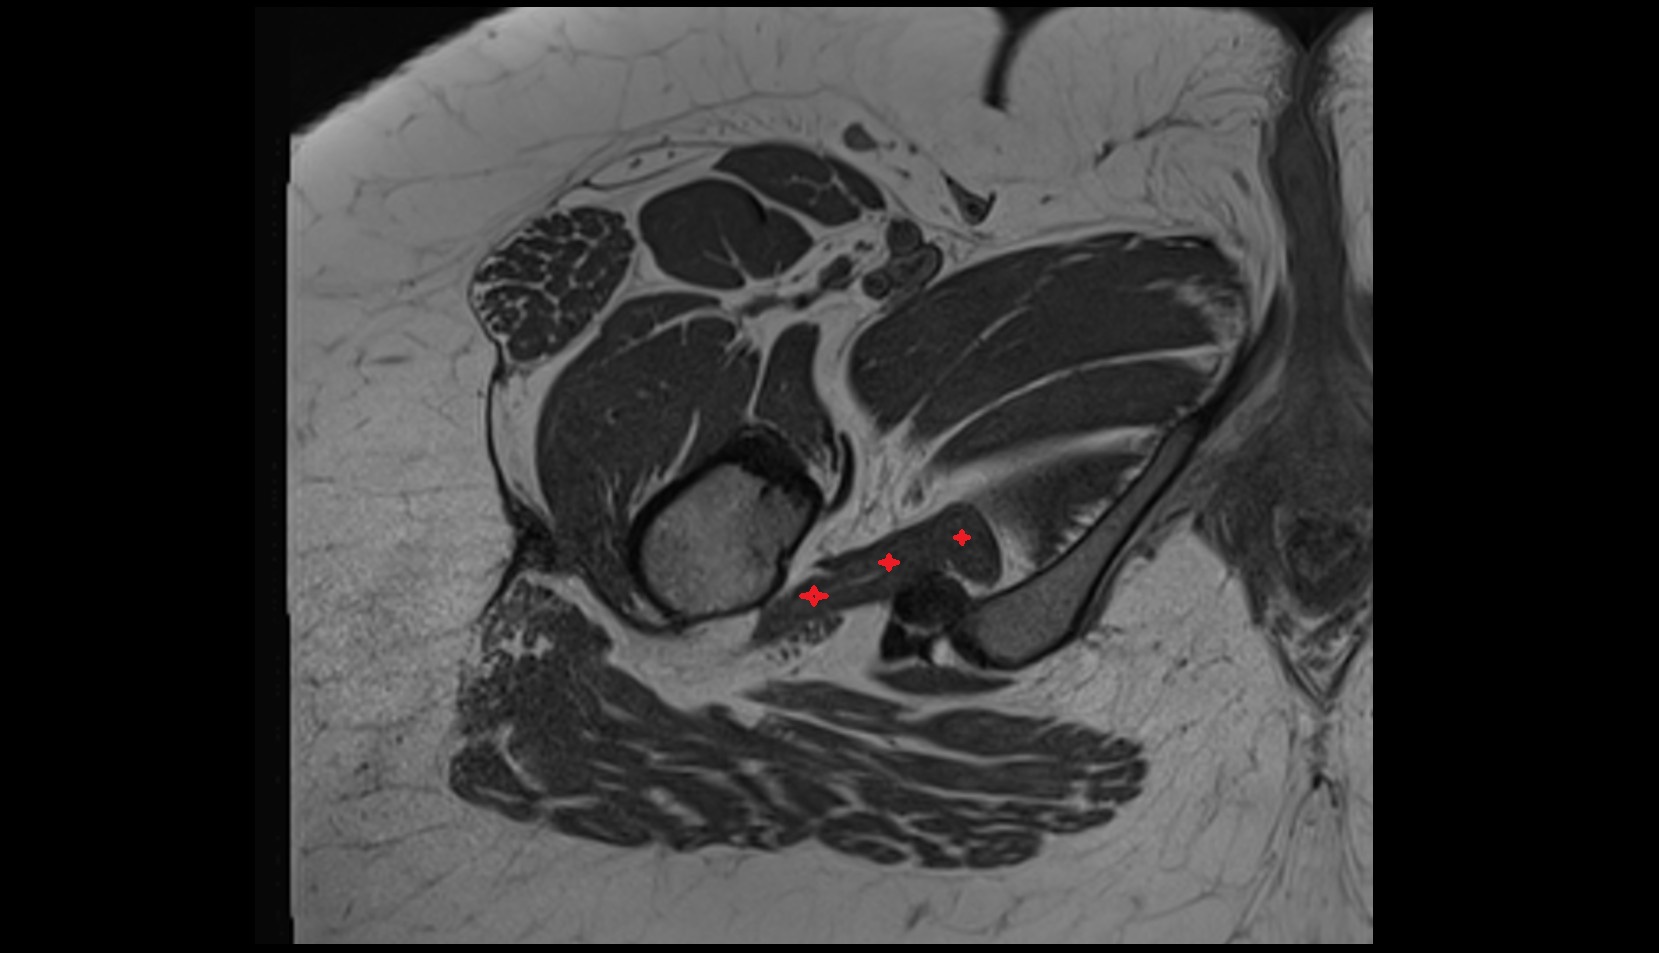

- Acetabular labrum